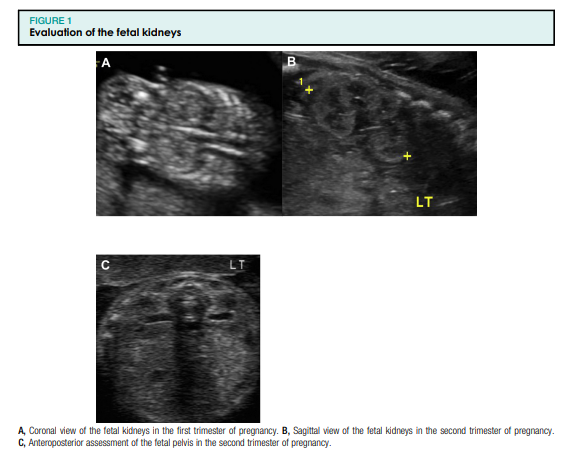

Loote urogenitaalsüsteem hõlmab loote neere, kusejuhasid, põit ning sise- ja välissuguelundeid. Loote urogenitaalsüsteemi standardne ultraheliuuring pärast raseduse esimest trimestrit hõlmab loote neerude ja põie visualiseerimist (joonised 1, A ja B ning 2). Neeruvaagna laienemist tuleks hinnata raseduse teisel ja kolmandal trimestril anteroposterioorse diameetri telgvaates (joonis 1, C). Loote suguelundeid tuleks uurida mitme raseduse ajal, kuna see võib aidata määrata koorionilisust või kui see on meditsiiniliselt näidustatud, näiteks kui patsiendil on X-seotud geneetilise häire oht (joonis 3). Lisaks tuleks mõõta lootevee mahtu (joonis 4), kuna see annab funktsionaalse hinnangu loote neerudele, mis toodavad lootevett pärast 16–17 rasedusnädalat. Neerupatoloogia võib seetõttu põhjustada nii lootevee mahu suurenemist kui ka vähenemist.